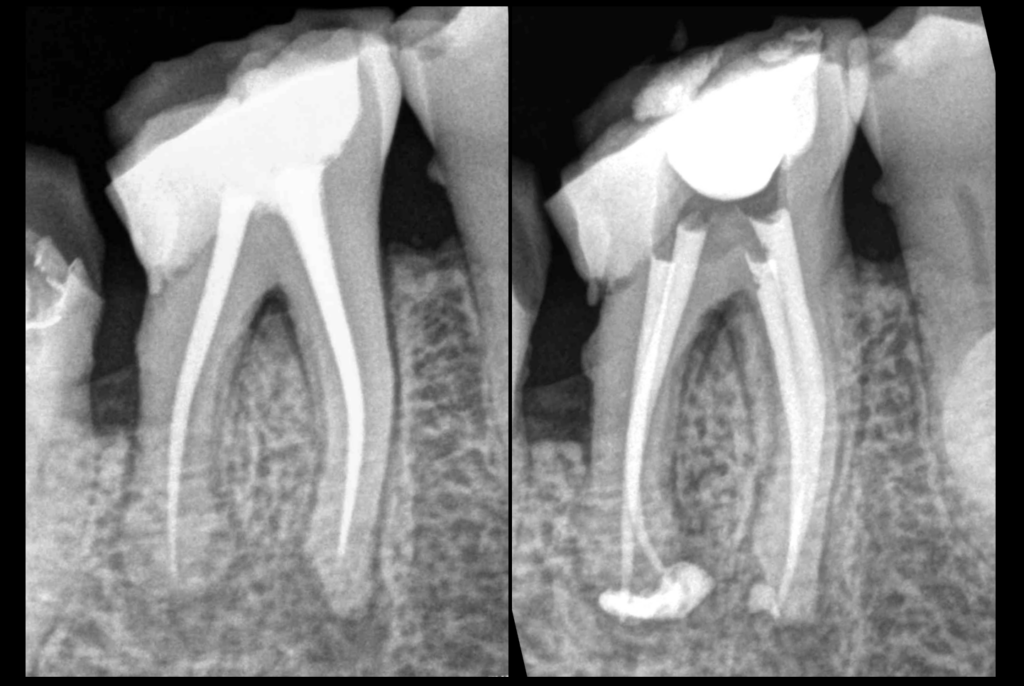

🔄 𝐋𝐞 𝐫𝐞𝐭𝐫𝐚𝐢𝐭𝐞𝐦𝐞𝐧𝐭 𝐜𝐚𝐧𝐚𝐥𝐚𝐢𝐫𝐞 𝐞𝐬𝐭 𝐢𝐜𝐢 𝐧𝐞́𝐜𝐞𝐬𝐬𝐚𝐢𝐫𝐞 pour prolonger la durée de vie de la dent, et corriger le problème infectieux/inflammatoire.

🦷 𝐔𝐧 𝐭𝐫𝐚𝐢𝐭𝐞𝐦𝐞𝐧𝐭 𝐩𝐚𝐫𝐨𝐝𝐨𝐧𝐭𝐚𝐥 𝐞𝐭 𝐩𝐫𝐨𝐭𝐡𝐞́𝐭𝐢𝐪𝐮𝐞 𝐯𝐢𝐞𝐧𝐝𝐫𝐨𝐧𝐭 𝐜𝐨𝐦𝐩𝐥𝐞́𝐭𝐞𝐫 𝐧𝐨𝐭𝐫𝐞 𝐭𝐡𝐞́𝐫𝐚𝐩𝐞𝐮𝐭𝐢𝐪𝐮𝐞 𝐞𝐧𝐝𝐨𝐝𝐨𝐧𝐭𝐢𝐪𝐮𝐞.